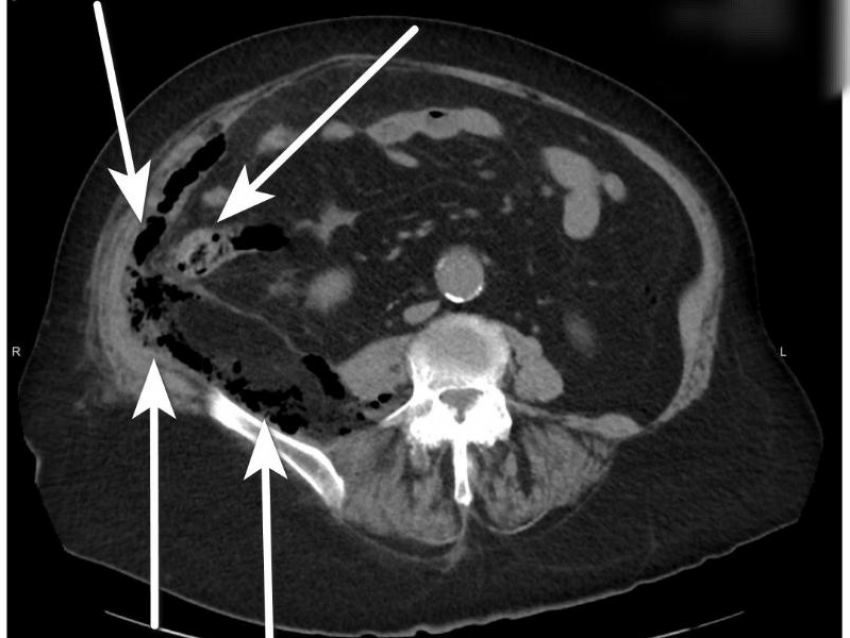

Осмотрев пожилую местную жительницу, врачи озвучили диагноз: острый деструктивный аппендицит, осложненный забрюшинной флегмоной.

«Острый аппендицит – одно из самых распространённых заболеваний, требующих своевременного вмешательства. В редких случаях он может осложниться развитием забрюшинной флегмоны – опасного состояния, при котором гнойное воспаление распространяется за пределы аппендикса в забрюшинное пространство», – сообщают в пресс-центре регионального минздрава.

Пенсионерке экстренно удалили аппендикс, выполнили санацию и дренировали все очаги гнойного воспаления. Из-за гнойного процесса, сахарного диабета и хронической почечной недостаточности послеоперационный период был тяжелым. Медикам удалось стабилизировать состояние женщины и избежать летального исхода.